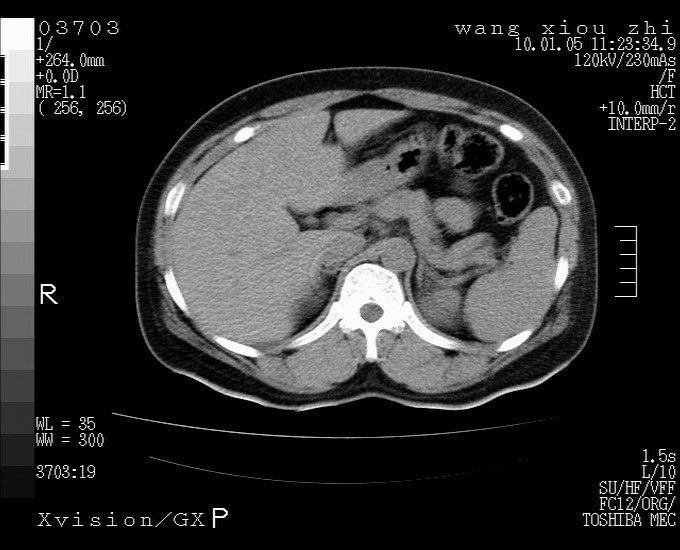

标题: CT23996:f,40.B超提示肿物。

左肾体积增大!下极见一密度略高团状软组织影!肾周结构组织未见明显异常!考虑左肾占位!建议增强!病史?

左肾占位性病变,建议增强。

左肾占位性病变,考虑肾癌,建议增强 。

左肾占位,肾门及腹膜后淋巴结肿大,考虑透明细胞癌可能性大,建议增强

左肾体积增大,内见肿块影,考虑占位,建议增强。